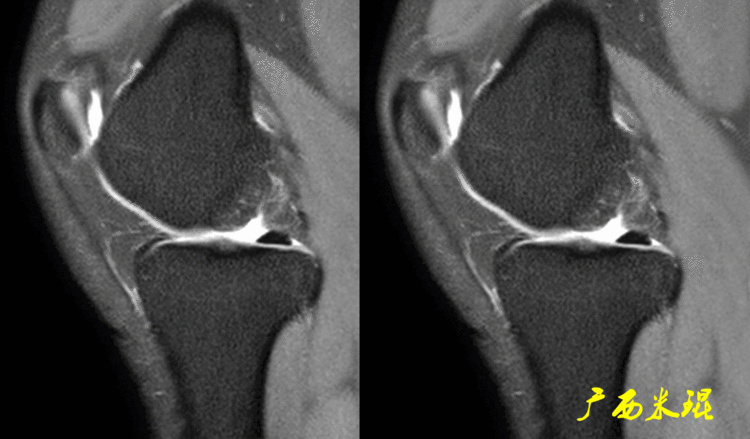

在腘肌腱裂孔区域,不论矢状位或者冠状位,抑或是轴位,MR显示两者之间都为高信号,下面这张MR是矢状位。

下面这张MR是冠状位,显示半月板与关节囊之间为高信号,半月板外上方中低信号影为腘肌腱。